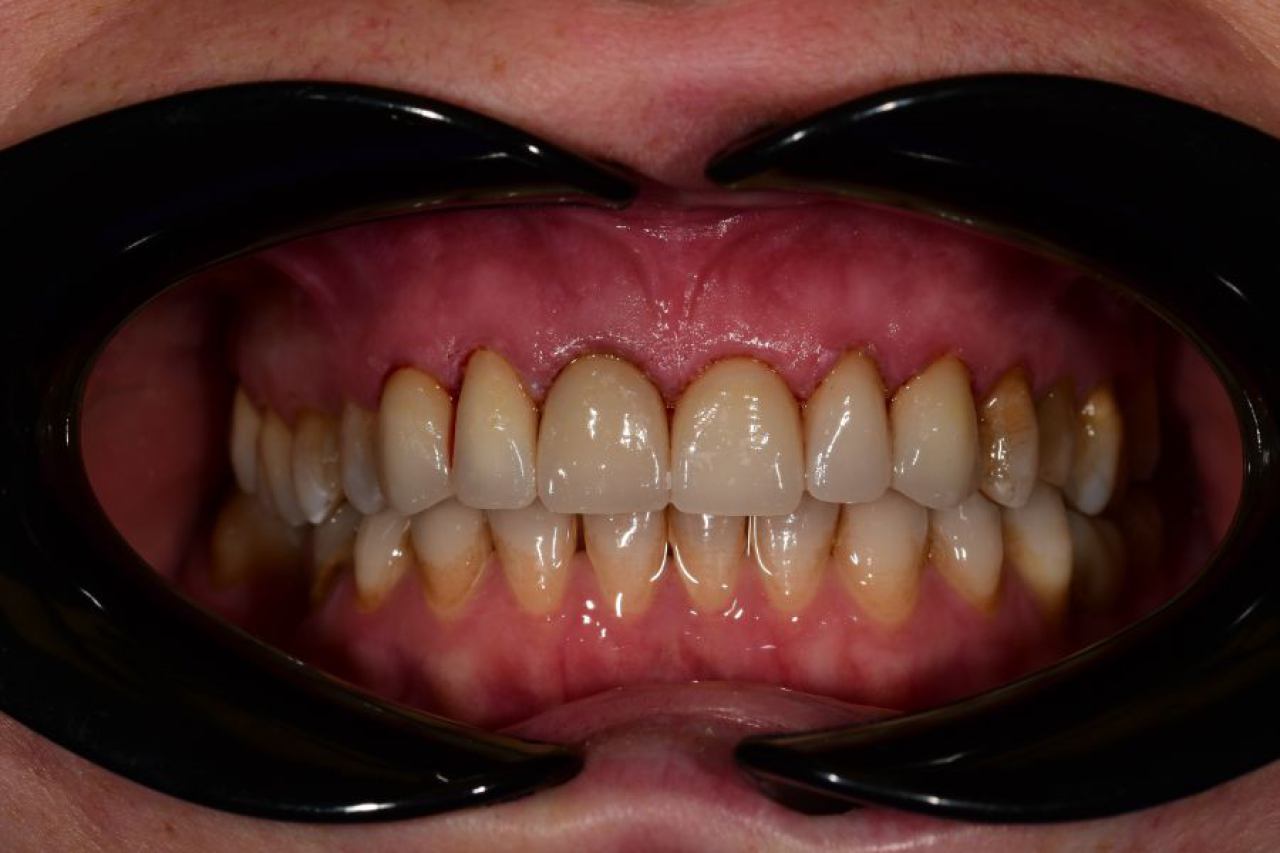

Protetika - mostovi i krunice

Dentalna protetika uključuje fiksne i mobilne radove kojima se nadoknađuje djelomična ili potpuna bezubost. Njihov cilj je povratiti funkciju žvačnog sustava i u konačnici, vrhunsku estetiku.

Marković Dental Clinic u svojoj ponudi ima metalkeramičke radove, potpunokeramičke radove, te u narodu zvane „bezmetalne", odnosno zirkonske radove.

Estetska dentalna medicina

Ukoliko niste zadovoljni svojim osmijehom tu je DSD ili Digital Smile Design kojim u okvirima naših mogućnosti ispunjavamo vaše želje „Hollywood smile" ljuskicama, minimalno invanzivnim preparacijama zuba.

Marković Dental Clinic uvijek na prvom mjestu ima zdravlje zubi i zadovoljstvo svakog pacijenta. Koristimo najmoderniji software gdje je pacijentu moguće virtualno prikazati nove zube te kasnije kreirati novi osmijeh protetskim radom, ljuskicama, krunicama ili mostovima.